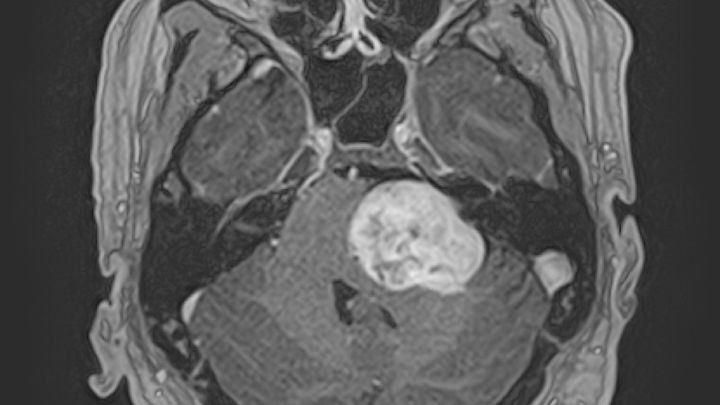

The type of tumor he has is Vestibular Schwannoma which is benign. The size of it is 4x3x3cm

He has sent his MRIs out to a few hospitals around the country and received a call from the best in the country, Dr. Friedman at University of California San Diego. At first Travis was not sure if he would be able to get in with this program because it’s a long wait. Dr. Friedman wants to operate on April 11th.